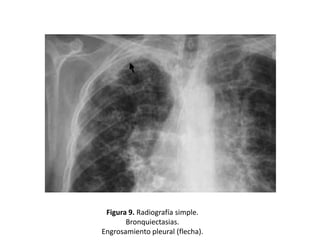

• La afectación pleural es rara, pero infecciones

repetidas que afecten a BQ subpleurales

pueden dar lugar a reacción pleural,

pudiéndose observar áreas focales de

engrosamiento. (Figura 9)

Figura 9. Radiografía simple.

Bronquiectasias.

Engrosamiento pleural (flecha).